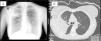

Chest X-ray (Fig. 1A) revealed alveolar infiltrate in the right upper lobe (RUL) with loss of volume. Chest CT (Fig. 1B) showed parenchymal consolidation with ground-glass opacities. R. mucilaginosa was isolated on two occasions from sputum cultures (Table 1). Fiberoptic bronchoscopy was performed, revealing transparent secretions with bloody traces originating in the RUL. R. mucilaginosa was also isolated from the bronchial aspirate (>105CFU/ml). Results from blood culture, Legionella/Pneumococcus antigens in urine, Mantoux, HIV serology, immunoglobulins, and sweat test were all normal. She was treated with amoxicillin-clavulanate for 14 days with full radiological resolution. The patient also underwent spirometric testing which was normal.

Fig. 1.

(A) Posteroanterior chest X-ray showing alveolar condensation and loss of volume in right upper lobe. (B) Chest computed tomography showing parenchymal consolidation and ground-glass opacities in right segment 3 and part of apical and anterior segments with air bronchogram and a fully patent bronchus.